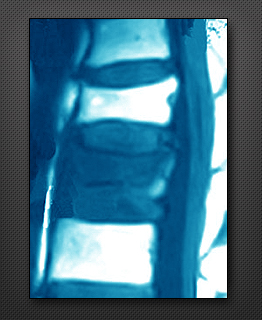

척추 전방 전위증

척추디스크와 후관절의 퇴행성 변화 또는 외상에 의해 척추마디가 불안정해져 척추뼈가 앞, 뒤로 튀어나오는 질환을 척추전방전위증이라 하며, 허리수술 환자의 15%를 차지할 정도로 디스크 다음으로 흔한 질환입니다.

척추 전방 전위증의 증례

척추 전방 전위증의 치료

요통이 주증상인 경우 운동과 함께 보조기 등으로 척추의 안정을 얻지만, 일상생활을 하기 힘들 정도의 통증이 있거나, 신경증상(마비)이 진행되면 수술이 필요합니다.수술은 요통의 호전과 하지 방사통을 제거하며 척추의 안정성을 유지합니다.